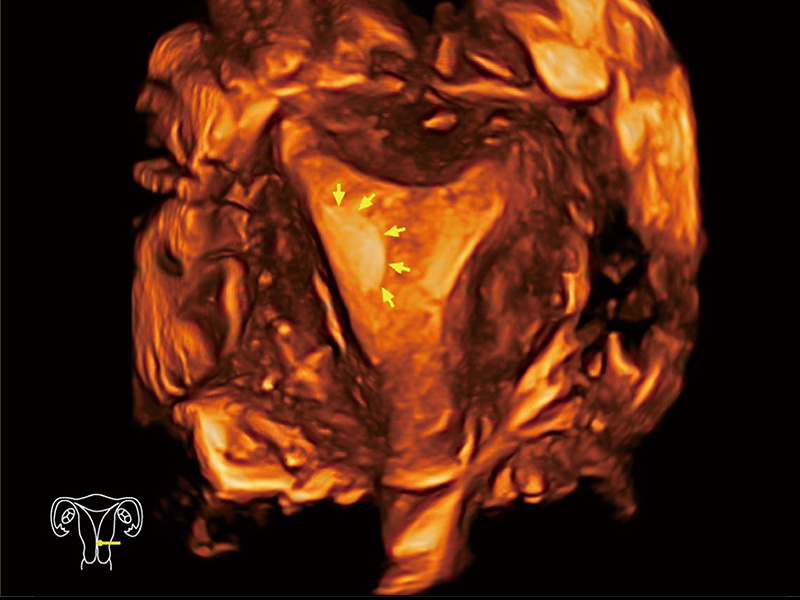

中央型宫腔粘连

单角子宫

腔内三维成像技术获得显著提升,超大扇角在满足日常基础扫查的同时,支持卵泡自动测量及多种三维渲染模式,为您提供更多的诊断信息,尤其是在子宫畸形的诊断,内膜及肿瘤占位观测中起到了重要的作用。